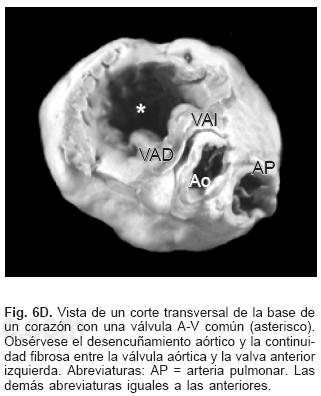

La anatomía básica de los 2 tipos de DSA–V fue la misma. Todos presentaron anillo fibroso A–V común, reducción de la distancia A–V–ápex e incremento de la distancia ápex –válvula aórtica, el tabique ventricular estuvo excavado (Figs. 4 y 6C), el anillo fibroso mostró dilatación anteroposterior, desencuñamiento aórtico, alteración en el esqueleto fibroso del corazón consistente en un anillo fibroso A–V común, ausencia del septum membranoso y persistencia de la continuidad entre la válvula aórtica y la válvula A–V común o válvula A–V izquierda (Fig. 6D), desviación anterior del tracto de salida del ventrículo izquierdo (Figs. 4 y 6C) y en dos especímenes obstrucción de éste por inserción en su interior de la valva anterosuperior izquierda (Fig. 7A). En un espécimen con una válvula A–V común se desarrolló una banda anómala de miocardio entre la pared libre y el tabique ventricular, lo que separó el componente derecho de la válvula A–V común en dos orificios valvulares (Fig. 7B). Las alteraciones asociadas se consignan en la Tabla III.

Se ha postulado que el defecto septal A–V es consecuencia de la falta de desarrollo y fusión de las almohadillas endocárdicas A–V dorsal y ventral, proceso anómalo que explica todas las alteraciones anatómicas presentes en esta cardiopatía.1,21 En vez de formarse dos anillos fibrosos como ocurre en el corazón normal se constituye uno común, dentro de él se forman dos válvulas A–V separadas o una válvula A–V común, lo que ha servido de base para la clasificación de esta cardiopatía congénita.2–4 Ambas formas tienen las mismas características patológicas básicas. Las dos válvulas separadas son de estructura trifoliada, la izquierda presenta 2 valvas septales anterior y posterior y una lateral, las valvas septales están separadas por una comisura que en el pasado se consideró erróneamente como una hendidura que según su extensión puede provocar insuficiencia valvular.23 Este concepto surgió debido a que la válvula A–V izquierda de esta cardiopatía se consideró homóloga de la válvula mitral del corazón normal, en realidad ambas son análogas, es decir cumplen una función similar pero tienen orígenes diferentes; ya se mencionó que en el corazón normal la valva medial de la válvula mitral deriva preponderantemente del componente izquierdo del tabique A–V doblado mientras que en esta cardiopatía la válvula A–V izquierda se origina de un nivel más inferior a partir del mesénquima que circunda el canal A–V común. En rigor en esta cardiopatía la válvula A–V izquierda no debe llamarse mitral, ya que su constitución es trifoliada, por lo que es preferible denominarla válvula A–V izquierda; las valvas septales de ésta se unen de manera continua a la cresta del tabique ventricular, con lo que queda obliterada la CIV perimembranosa y de entrada. Este hecho es determinante del establecimiento del cortocircuito por encima de las valvas A–V; el espacio entre éstas y el borde inferior del tabique interatrial comúnmente se ha considerado como FP, que en realidad es la suma del DSA–V y del FP; cuando éste está presente el borde inferior del tabique interatrial es cóncavo y queda por encima del plano del anillo fibroso A–V. Se han descrito casos en que dicho borde inferior no es cóncavo sino recto y coincide con el plano A–V, situación en la que está ausente el FP y el cortocircuito interatrial se establece a nivel del defecto septal A–V.2,9 Cuando se desarrolla una válvula A–V común con su patrón de cinco valvas, la gran comunicación permanece permeable.1,2,16,21